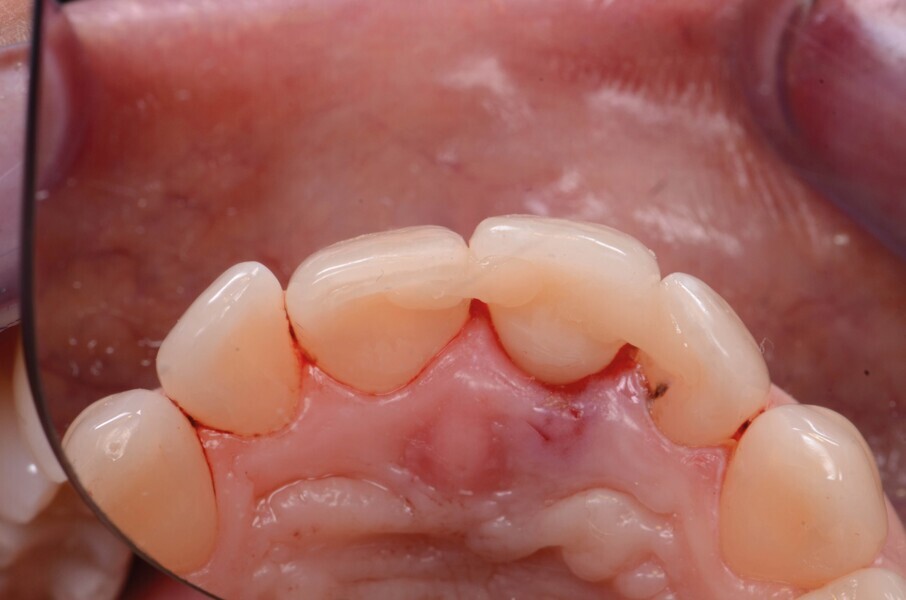

Fig. 2a : Vue préopératoire intraorale

Une fistule avec écoulement purulent est présente en regard de l’apex de la dent. Une tomodensitométrie volumique a faisceau conique (CBCT) est réalisée pour évaluer l’environnement péri-dentaire : l’épaisseur de l’os vestibulaire, la forme de l’alvéole et la position de la racine sur le plan sagittal (Figs. 2–3). Une fracture radiculaire est mise en évidence.

Dans le cas de la patiente, les tissus mous sont bien positionnés : la dent a subi une égression, mais aucune récession n’est présente. L’os vestibulaire est partiellement absent et classe l’alvéole dans le type II selon Elian et al.2

L’aspect le plus difficile est ici le maintien de l’architecture des tissus mous et des papilles adjacentes. Etant donné la déhiscence osseuse importante, un protocole de préservation alvéolaire est mis en place. L’objectif est de préserver les tissus adjacents et de limiter toute résorption osseuse.